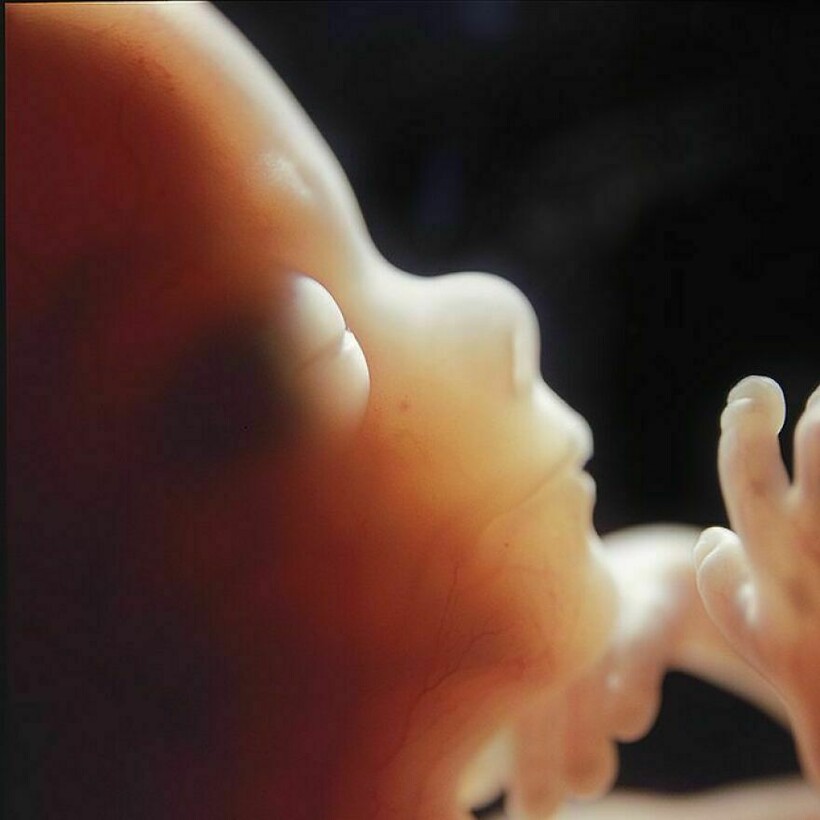

Леннарт Нильссон стал настоящей легендой фотографии, ведь он сделал то, чего не удавалось никому: показал миру, как развивается ребенок в утробе матери. Его проект «Ребенок родился» был создан в 1960-х годах, и он представляет собой детальные снимки эмбрионов на разных стадиях развития. Фотографии стали сенсационными, впервые они появились в журнале LIFE, и одна из них украсила обложку. На протяжении многих лет эти снимки публиковали в разных журналах.

Фотограф снимал детей в утробе матерей во время медицинских процедур

Он присутствовал на амниоцентезе и лапароскопии

Нильссон не скрывал, что снимал и эмбрионы после выкидышей и абортов

Снимки стали сенсацией, их много раз перепечатывали, они и сегодня вызывают отклик у зрителей

Его фото позволили заглянуть в чудо рождения, они стали источником знаний и вдохновения

Почти все эти снимки сделаны в 1965 году, однако Нильссон фотографировал до конца своей жизни, и запечатлел не только развитие эмбриона, но и само зарождение жизни: вот тут мы собрали другие его фотографии.